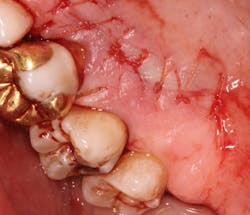

A split- to full-thickness intrasulcular incision was made on the facial of teeth Nos. 2 through 4. Upon completion of flap elevation, an intraosseous cyst associated with the distobuccal root of No. 3 was noted perforating the buccal plate and adherent to the overlying flap (figure 2). A sharp dissection separated the cyst from the flap (figure 3), and the cyst—measuring roughly 1.0 x 0.75 x 0.5 cm—was enucleated intact, leaving an intraosseous defect (figures 4a and 4b).